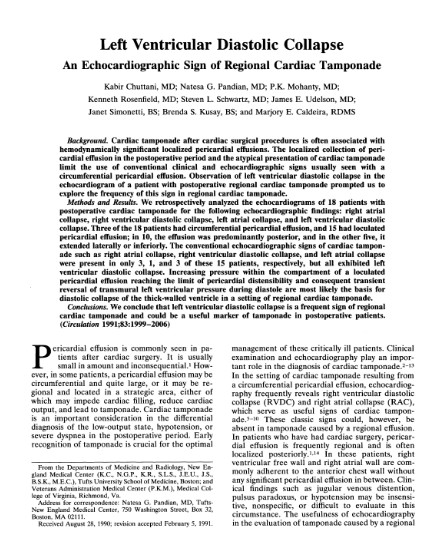

O colapso diastólico do VE foi descrito pela primeira vez por Chuttani et al., quando foi observado ser uma causa frequente de tamponamento após cirurgia cardíaca por presença de aderências entre as cavidades direitas do coração e a parede torácica, com tendência a uma localização mais posterior.